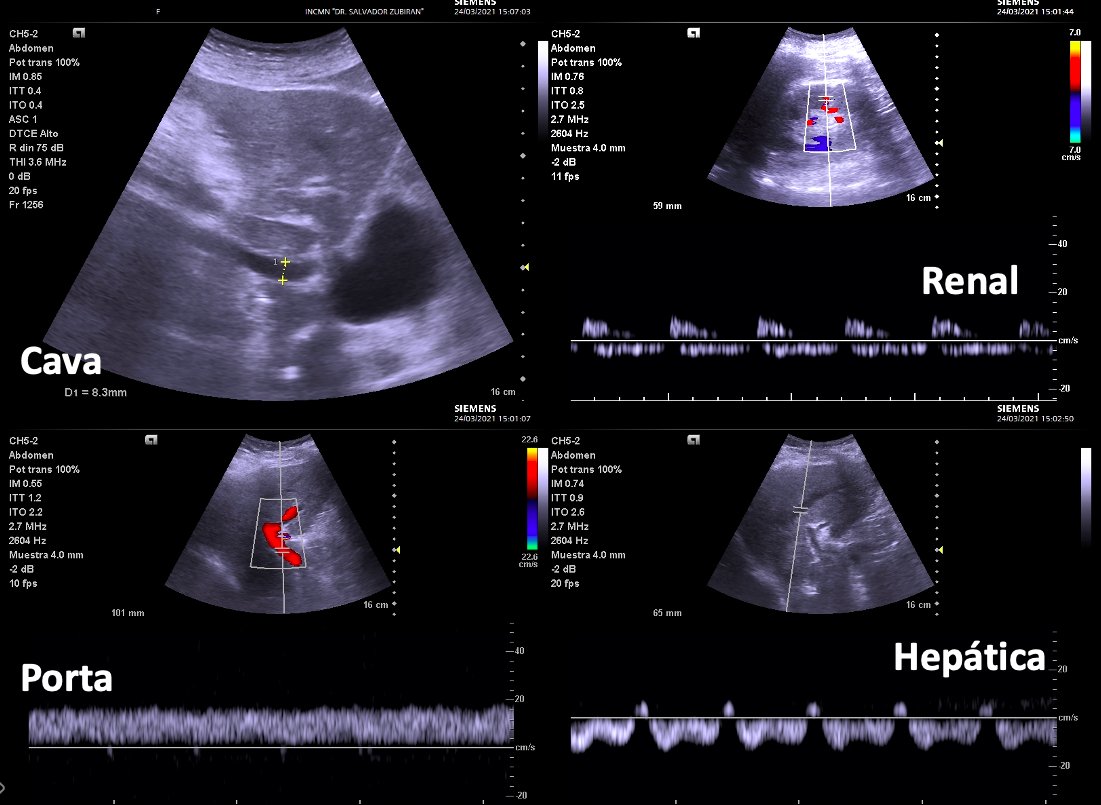

Another one for the AKI Consult series 🧵: 👵 w group 4 Pulmonary Hypertension. Recently 🏥 w severe congestion and AKI 2/2 cardiorenal syndrome with a Cr of 3.5 mg/dl. (Baseline Cr 0.5 mg/dl) After ultrafiltration and IV diuretics the pt was decongested and AKI resolved.. 1/11